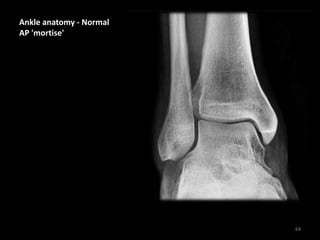

Ankle anatomy - Normal

AP 'mortise'

• The weight-bearing

portion is formed by

the tibial plafond and

the talar dome

• The joint extends into

the 'lateral gutter' (1)

and the 'medial gutter'

(2)

• The joint is evenly

spaced throughout